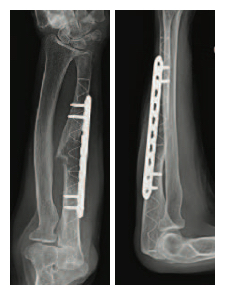

Diagnosis: Metastatic Renal Cell Carcinoma with pathologic fracture of the right radius and left ulna and significantly compromized bone quality.

Description of treatment: Radiation to lesion followed by surgery utilizing two IlluminOss implants sizes: 11 mm x 180 mm in the radius augmented with a 3.5 mm small fragment LCP plate and 11 mm x 220 mm in the ulna augmented with a 3.5 mm small fragment LCP plate. To insert each implant, a small incision was made and an awl inserted. This was followed by the use of a reamer to create a pathway for the implant to be inserted into the intramedullary canal. A strong, PET (Dacron) balloon catheter was inserted into the intramedullary canal and infused with a 3 part multi-functional, methacrylate, photodynamic liquid monomer. A light box emitting visible blue light (436 nm) hardened the implant on demand. The implants provided immediate strength and rotational stability. Dr. Williams chose to utilize plates in conjunction with the IlluminOss implants due to the patient’s significantly compromised bone quality. The implants created a stable construct enabling the plates to be secured which was not achievable with hardware alone in this severely deteriorating and fragile bone.

Left Ulna

6 Week Post-op